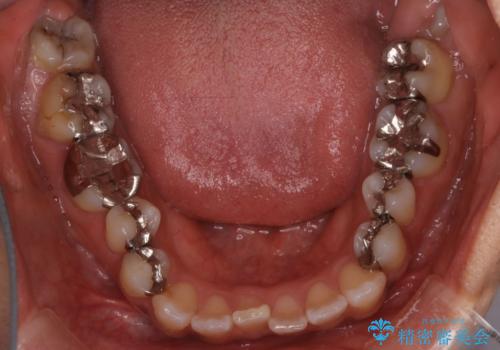

【インビザライン】前歯の凸凹をなおしたい

- 前歯の凸凹を主訴に来院されました。

インビザライン にて治療を行い、歯並びの改善を行うことができました。